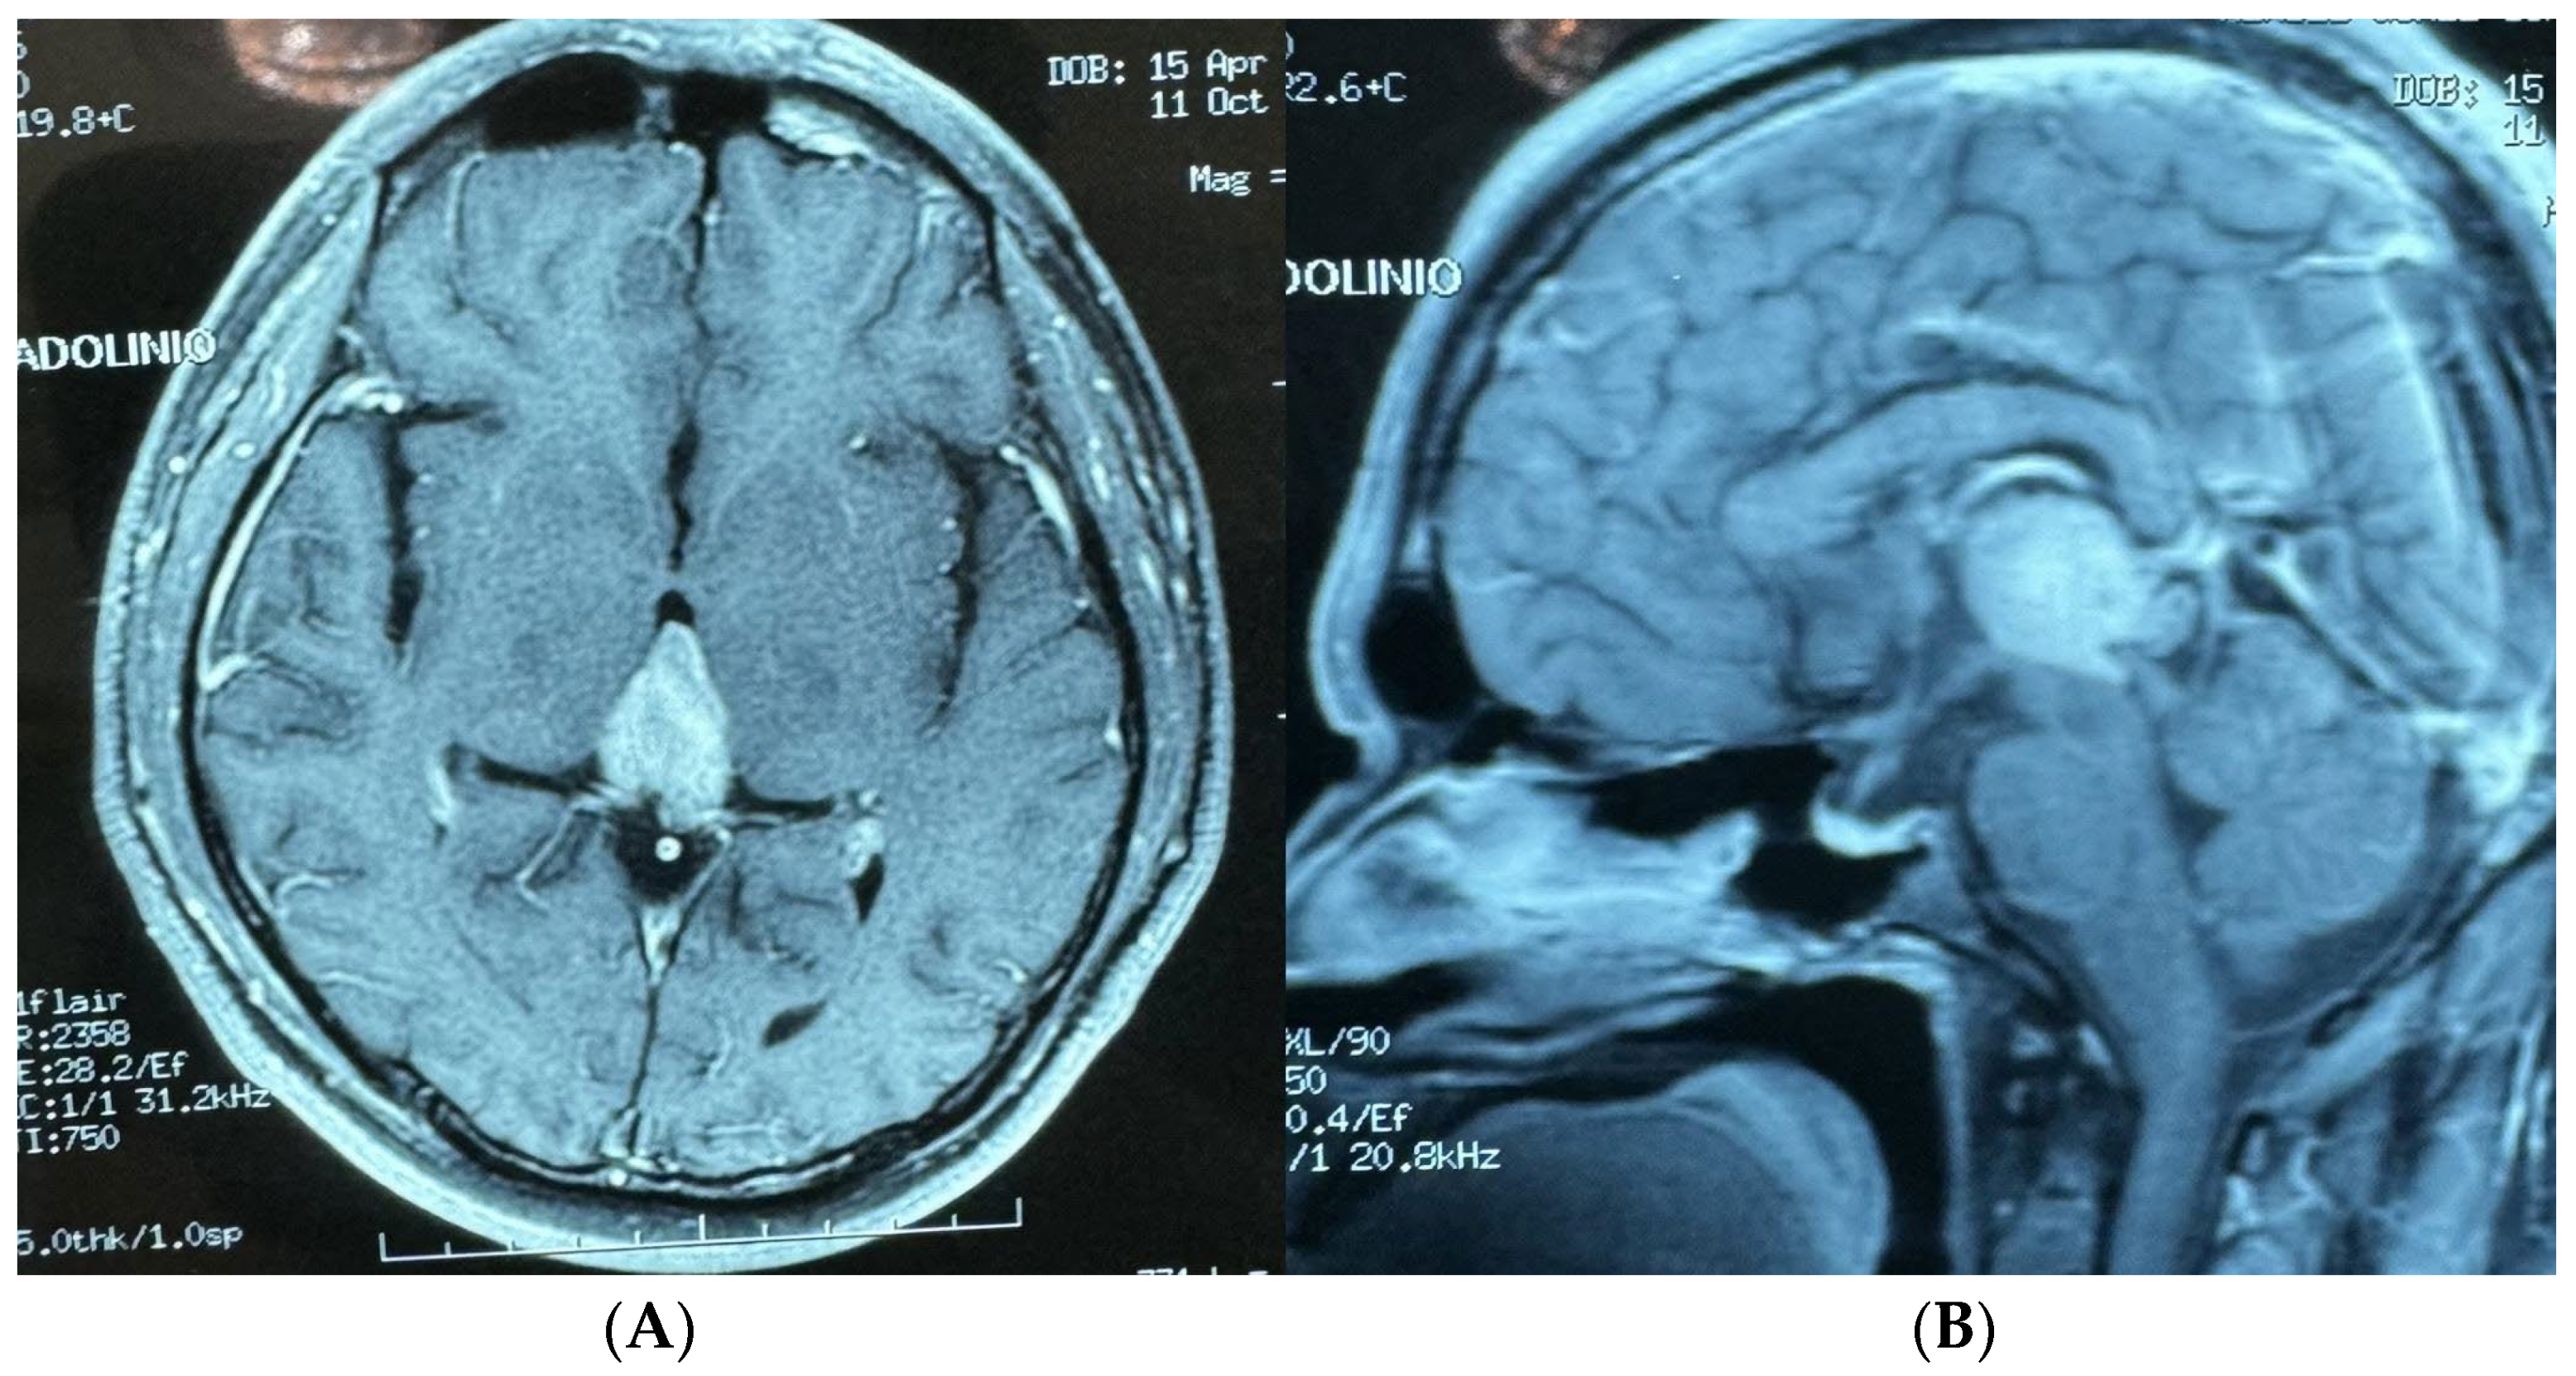

- Case 2: The AR-assisted transtentorial approach enabled near-total resection of a pineal region ependymoma, illustrating the technology’s efficacy in managing deep-seated tumors with complex vascular relationships; guided by AR to the pineal region where the tumor was located, in turn, AR allowed us to know the limits of the tumor; those limits were blocked to direct vision by the parenchyma and vascular structures (in-ferior sagittal sinuses, internal cerebral veins, basal of Rosenthal, vein of Galen, rectus, and inferior longitudinal sinus).